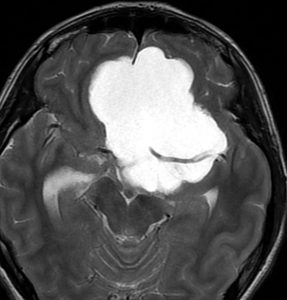

この子の症状は頭痛だけ。両親はなぜ気づかなかったのかと疑問を持ちますが,巨大になるまで症状が出ないこともあるのです。左のCTで腫瘍の周囲にバラバラと白い点状の石灰化があるので診断できます。左の視床下部から発生したクラニオでした。開頭手術しますが超高難易度です,怖いです (┯_┯) 複数回開頭手術になりましたが結果的に全摘出できています (by Dr 山本哲哉)。

危険な のう胞性 頭蓋咽頭腫 cystic craniopharyngioma

上に示した例は,巨大な「のう胞性」頭蓋咽頭腫でもあります。袋の中に液体が入っているのを「嚢胞 cyst」といいます。大部分は液体なので,袋を破れば腫瘍は簡単に小さくなります。